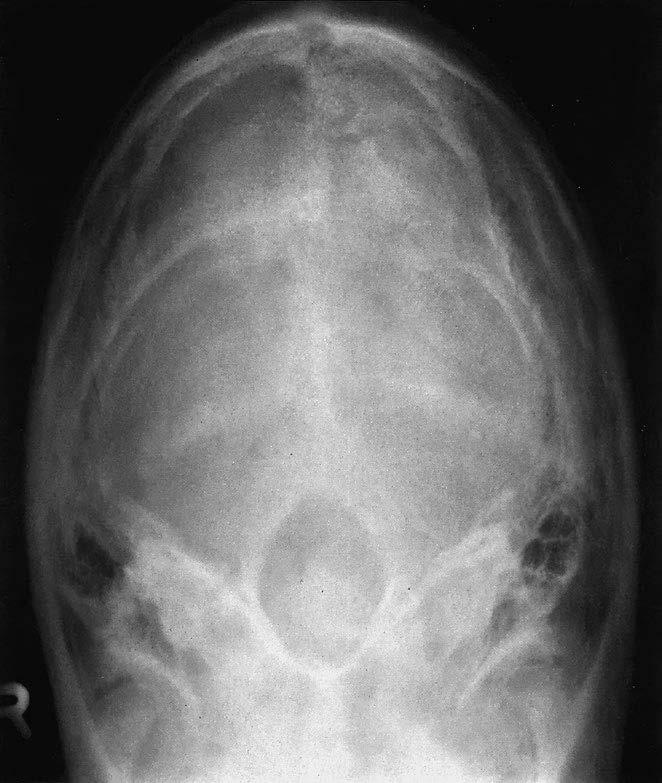

1 sutura lambdoidea (šev lambdový)

2 protuberantia occipitalis (externa a interna)

3 os occipitale (kost týlní)

4 sulcus sinus transversi

5 crista occipitalis

6 foramen magnum

7 hrana pyramidy (kosti skalní)

8 eminentia arcuata

9 jádro labyrintu

10 cellulae mastoideae (mastoidní sklípky / dutinky v processus mastoideus)

11 meatus acusticus internus (vnitřní zvukovod)

12 arcus posterior atlantis (zadní oblouk nosiče)

13 foramen jugulare

14 dens axis (zub čepovce)

15 articulatio temporomandibularis (čelistní kloub)

16 caput mandibulae (hlavice dolní čelisti)